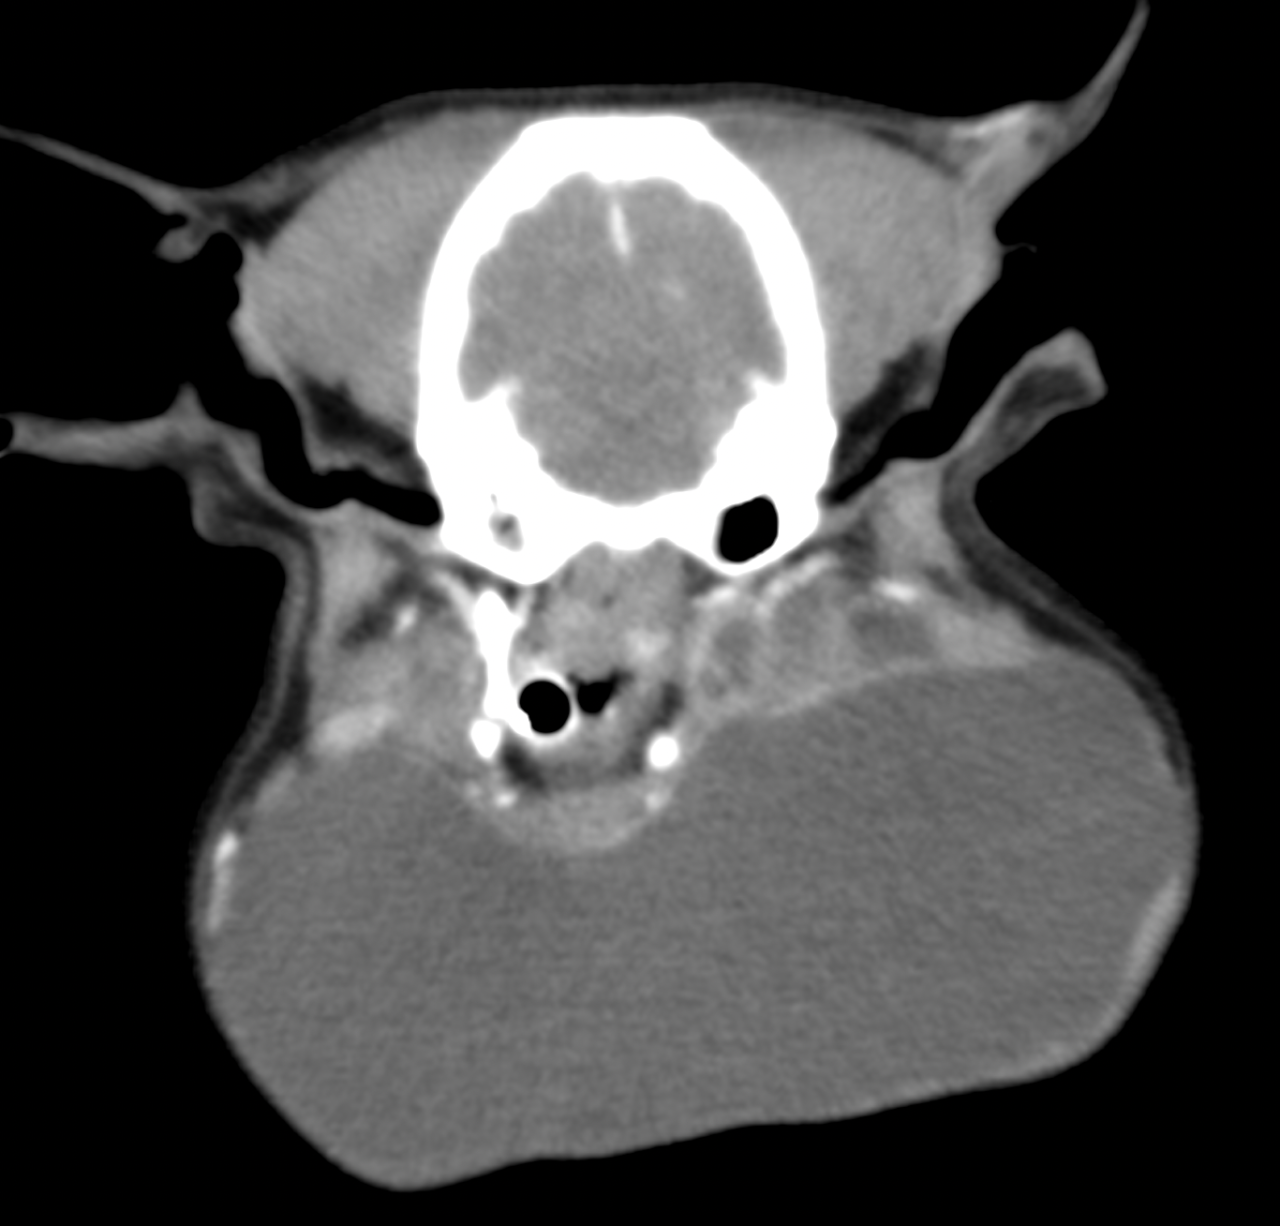

画像診断:超音波検査: 腫瘤内部に低エコー域を確認、液体貯留を示唆。CT :耳下腺の拡張および嚢胞形成を確認。穿刺液検査: 黄色透明の粘液、唾液腺の内容物と一致。診断: 唾液腺嚢胞。切除が推奨される状態。手術手技:唾液腺摘出:病変を含む唾液腺の完全摘出を実施。唾液管を追跡し、嚢胞部を完全切除。閉塞の原因と考えられる唾石様物質の摘除を行う。